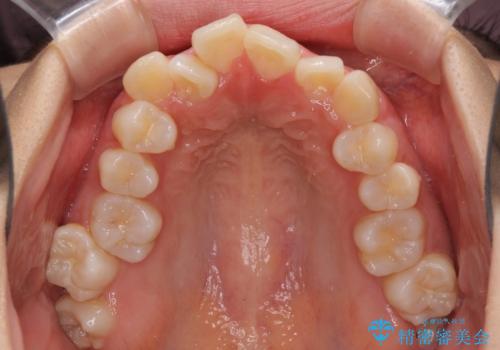

口元の突出感を改善 2年弱での抜歯矯正

- 出っ歯とデコボコを気にして来院された患者様です。

口元の突出感を改善するため、上下左右第一小臼歯4本の抜歯を行い、ワイヤー装置による矯正治療を行うこととしました。

治療前の上下正中はずれていましたが、骨格的な上下左右差はあまり認められなかったため、正中を揃えて治療を終えることができました。

1年半ほどで治療を終えることができるとは我々も想像しておらず、患者様には大変満足していただきました。